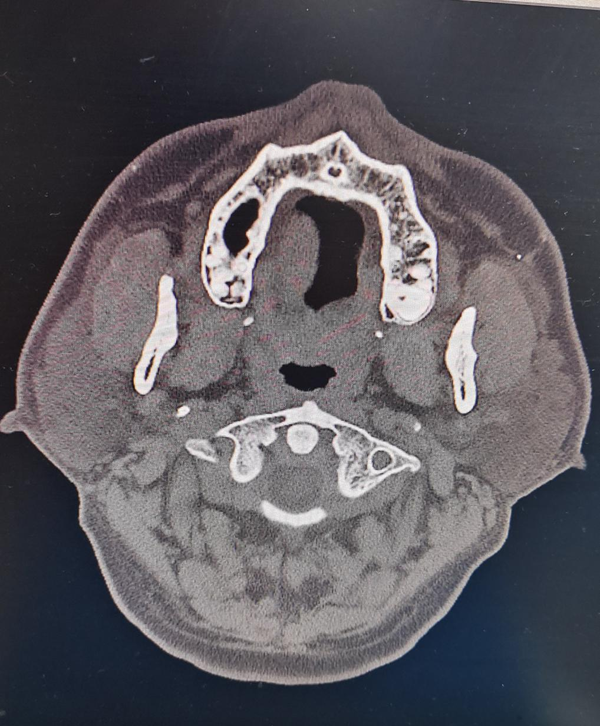

于主任看病人后说道:这个病人一个眼大一个眼小(图1),随后其详细询问了患者的病史、病情,原来他的头晕是老毛病了,从一次意外的颈椎牵引伤开始,他就断断续续的头晕,从一开始每天10余分钟,休息后可缓解,到现在一坐起和站立后就心慌头晕,已严重影响正常生活,这整整有十余年的时间。在这期间,他辗转于省立、齐鲁医院及省外多家医院就诊,各种止晕、扩血管、改善循环治疗均不明显。此时于主任的心中已基本有了定论:给患者完善个颈椎检查吧,他的左眼裂明显小于对侧,符合霍纳综合征,非常有可能是个交感神经型颈椎病的患者。随后完善的颈椎CT示:C3/4椎间盘突出。齿状突与两侧块间距不等,请结合临床除外寰枢关节半脱位可能(图2)。考虑寰枢椎半脱位、颈椎间盘突出导致颈椎不稳,站立时影响交感神经,出现以上症状。我们建议患者坐立位时佩戴颈椎牵引器、休息时配合理疗,辅以营养神经、改善肌紧张治疗后,患者头晕明显好转,心慌症状也得以改善。在患者出院之际,大夫贴心地告知他:颈托固定、理疗等可短时间内缓解症状,若想进一步积极治疗,可至神经脊柱脊髓外科行手术治疗。